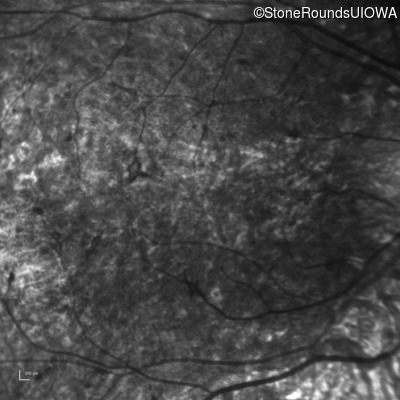

Infrared Fundus Photograph - Right - 5/200

Exemplar